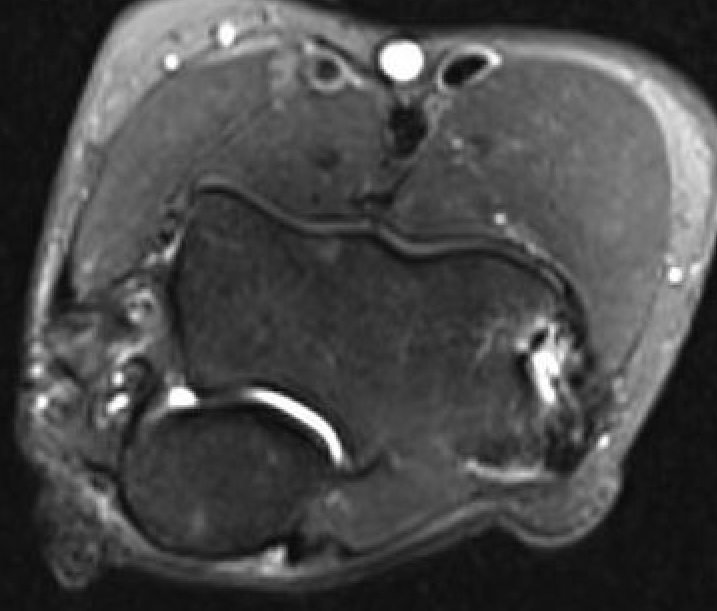

MRI

High grade partial tears of ECRB on lateral eipcondyle

Tendonopathy of the common extensor origin, with thickening and high grade tear partial tear

Tendonopathy of the common extensor origin, with thickening and high grade tear partial tear